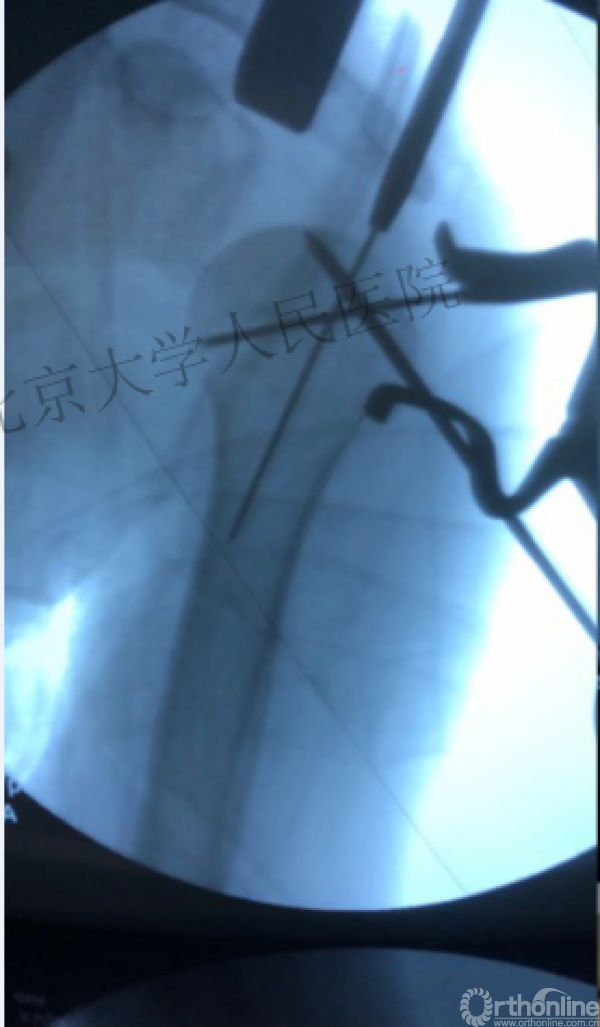

术中片

进钉更完美——我们的帮助

可否有更好的进钉和复位的更好帮助办法?